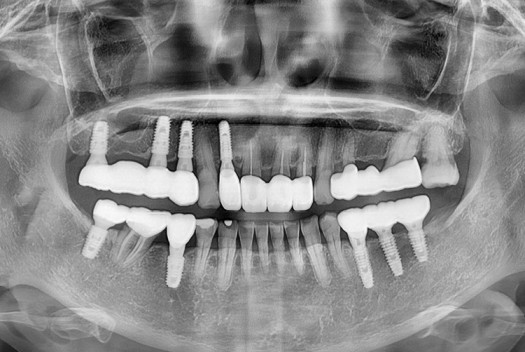

[임플란트] 임플란트

치료전 : 2015-07-04

세종치과는 많은 환자와 다양한 케이스를 바탕으로 항상 편안한 임플란트 수술을 제공하고자 노력하고,

오래동안 튼튼히 쓸 수 있는 임플란트 수술을 가장 큰 목표로 삼고 있습니다.